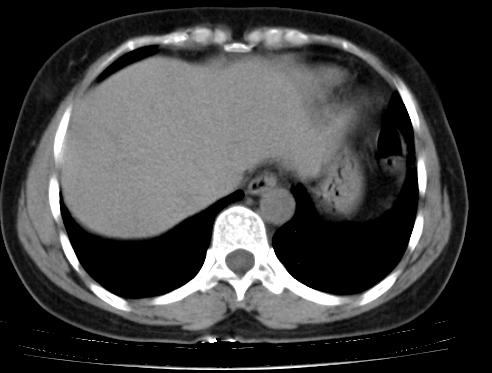

标题: CT25227:背部疼痛伴双侧胸壁痛2月,食欲差。 [打印本页]

标题: CT25227:背部疼痛伴双侧胸壁痛2月,食欲差。

肺结核并胸椎结核?请各位高手指教。

用椎体的条件来扫胸椎呀!考虑1左侧胸膜小结节形成2椎体结核并冷脓肿形成

考虑胸椎结核并椎旁软组织肿胀。

左肺结核灶,胸椎结核并冷脓肿。

左肺结核灶,胸椎结核并冷脓肿